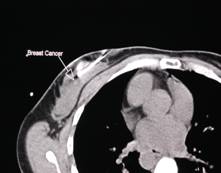

STEP 3:

radiology

This step is taken by a

QHM® interventional

radiologist to verify the exact area of this early cancer mass

which was missed weeks earlier by mammography. Prior to her

appointment with the radiologist, she was sent for a breast

MRI which also showed the mass that mammography had

missed.

STEP 4: CAT

scan

This step was taken solely for the

benefit of those individuals who would try to discredit this

technology. NCIT's founder, Robert Dowling, wanted to

prove that the mass was, in fact, cancer -- and, of course, it

was. With QHM®

technology, a biopsy is no longer necessary. A

"guiding" CAT scan is used for the proper placement of the

ablation device to kill the tumor. The CAT scan is a second

proof of the cancer.